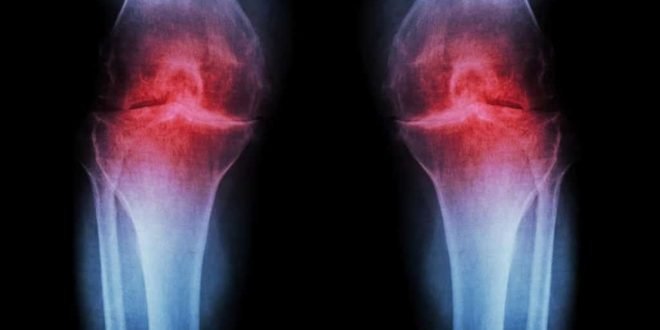

osteoarthirtis

Konsumsi Glukosamin Tidak Membantu Pasien Radang Sendi, Bahkan Membahayakan